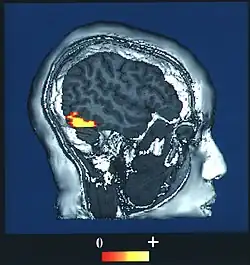

| The fusiform face area, the part of the brain associated with facial recognition | |

Prosopagnosia (from Greek prósōpon, meaning "face", and agnōsía, meaning "non-knowledge"), also known as face blindness,[2] is a cognitive disorder of face perception in which the ability to recognize familiar faces, including one's own face (self-recognition), is impaired, while other aspects of visual processing (e.g., object discrimination) and intellectual functioning (e.g., decision-making) remain intact. The term originally referred to a condition following acute brain damage (acquired prosopagnosia), but a congenital or developmental form of the disorder also exists, with a prevalence of 2.5%.[3] The brain area usually associated with prosopagnosia is the fusiform gyrus,[4] which activates specifically in response to faces. The functionality of the fusiform gyrus allows most people to recognize faces in more detail than they do similarly complex inanimate objects. For those with prosopagnosia, the method for recognizing faces depends on the less sensitive object-recognition system. The right hemisphere fusiform gyrus is more often involved in familiar face recognition than the left. It remains unclear whether the fusiform gyrus is specific for the recognition of human faces or if it is also involved in highly trained visual stimuli.

Prosopagnosia can be caused by lesions in various parts of the inferior occipital areas (occipital face area), fusiform gyrus (fusiform face area), and the anterior temporal cortex.[9] Positron emission tomography (PET) and fMRI scans have shown that, in individuals without prosopagnosia, these areas are activated specifically in response to face stimuli.[6] The inferior occipital areas are mainly involved in the early stages of face perception and the anterior temporal structures integrate specific information about the face, voice, and name of a familiar person.[9]